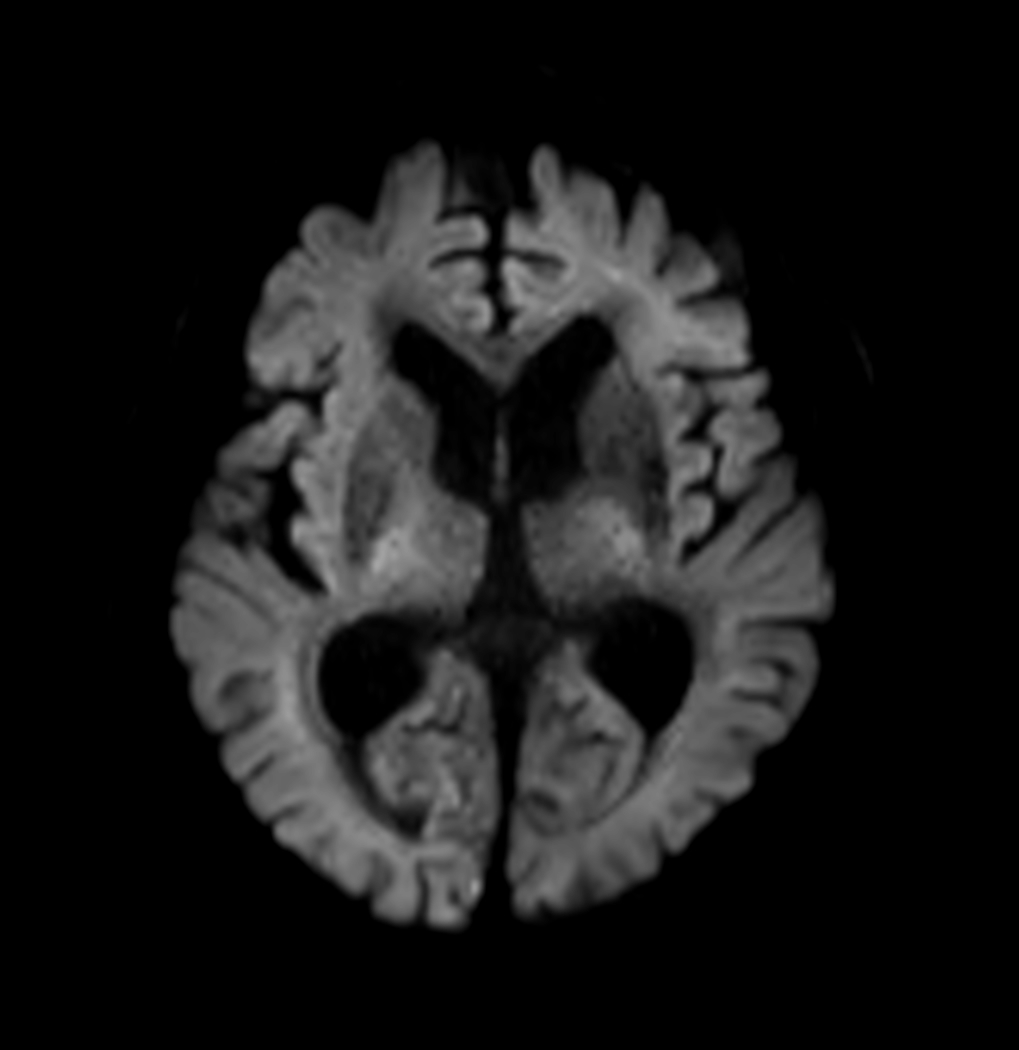

DWI (b1000)